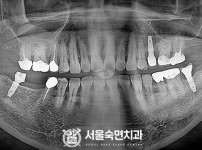

임플란트-전후사진1

임플란트-전후사진2

임플란트-전후사진3

임플란트-전후사진4

치과를-선택할-때-꼭-확인하세요-서울숙면치과-임플란트-전후사진